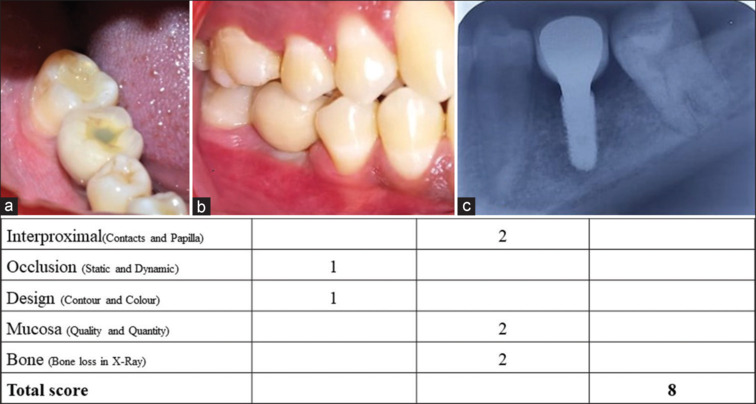

Materials and methods: Fifteen patients with cement-retained single-implant crowns in the posterior region of the jaws were included. Eight examiners, two prosthodontists, two periodontists, two oral surgeons, and two orthodontists evaluated 15 photographs of single-unit implant crowns during the 1-year follow-up examination. The examiners assessed the photographs for FIPS, which includes five parameters for objectively evaluating the single-unit implant crowns. Assessments were performed twice at a gap of 4 weeks.

Results: The mean total FIPS scores for all included examiners were 7.133 for time T1 and 7.074 for time T2, showing a strong Pearson correlation coefficient for intra-examiner reproducibility. No significant difference was analyzed among different specialties with statistically significant values of the Kruskal-Wallis test.